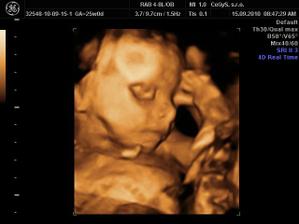

Náš anjelik🙂